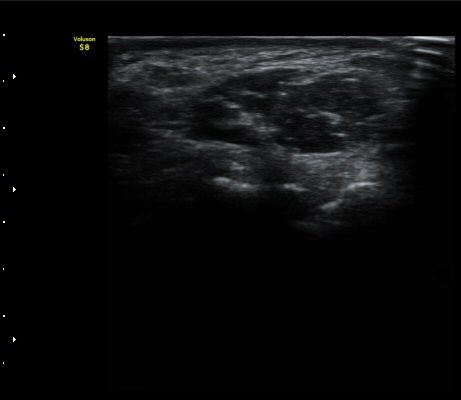

¼ÒÁö±¸ ³»Ãø¿¡ ȾÀ¸·Î ŽÃËÀÚ¸¦ ´ë¾î °¥°í¸®»À °¥°í¸® ³»Ãø¸é ÇÇÁú°ñÀ» °üÂûÇÏ´Ï(¾Æ·¡ ±×¸²)

°¥°í¸® ÇÇÁú°ñ ¿¬¼Ó¼º ¼Ò½Ç(loss of cortical continuity of hook of hamate)ÀÌ °üÂûµÈ´Ù(±×¸² 1, 2).

ÇÇÁú°ñ ¿¬¼Ó¼º ¼Ò½ÇÀº °ÇÃø°ú ºñ±³ÇØ¸é ´õ¿í ¶Ñ·ÈÇÏ´Ù(±×¸² 3, 4).